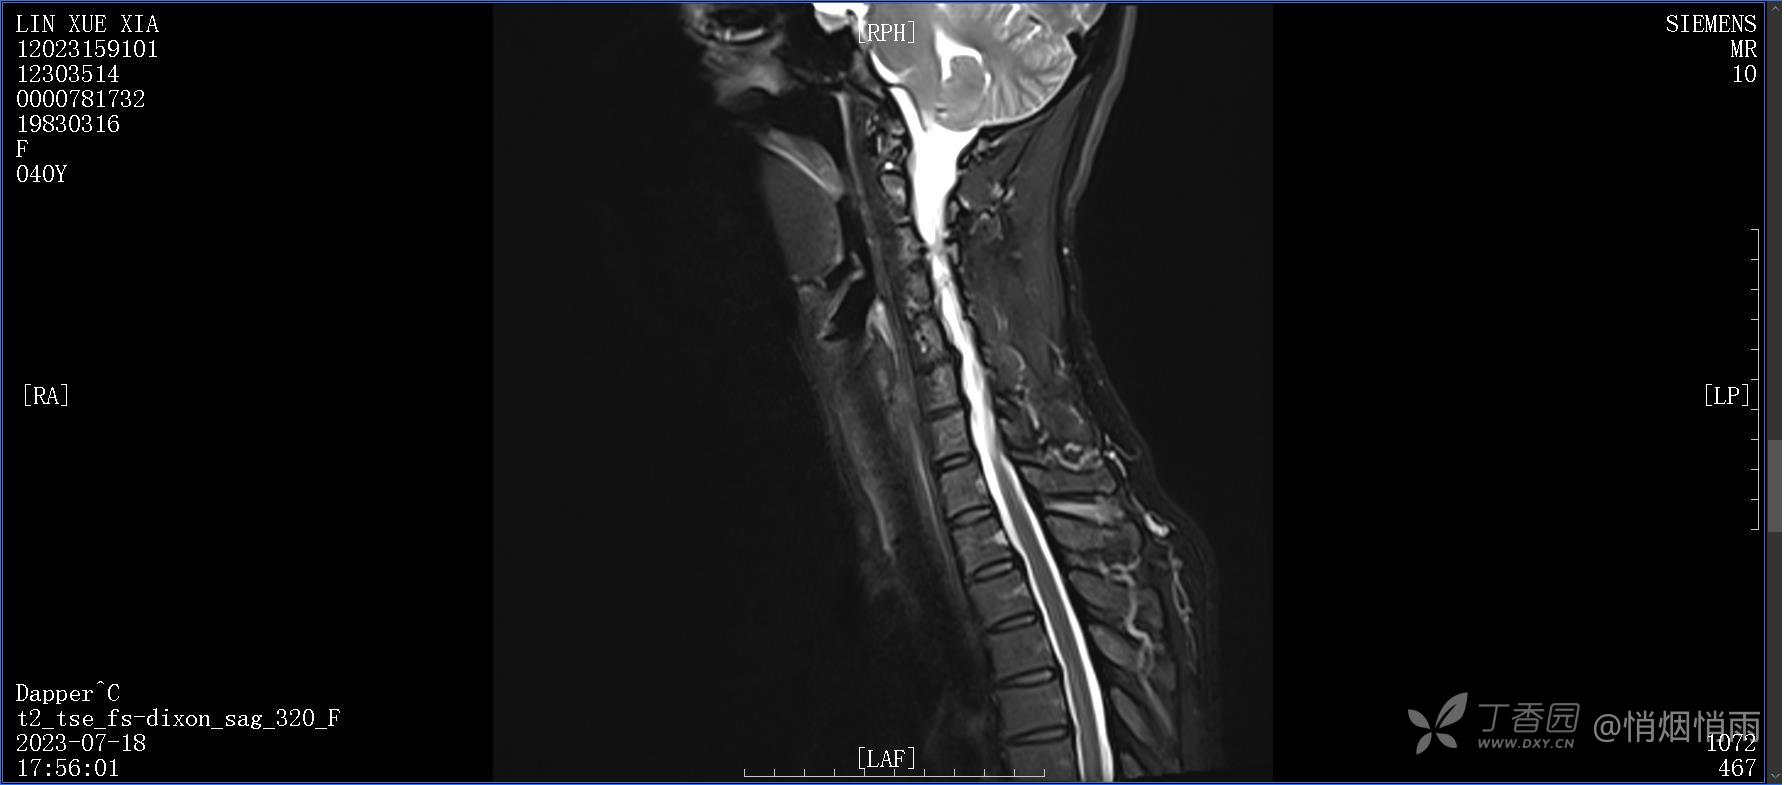

不明原因的右肩背部疼痛

NeurothinkerZ 推荐患者女性,40岁,因右肩背部疼痛班活动受限4日余入院(2023-07-17)。

病史:入院前4天无明显诱因突然感右肩背疼痛伴随活动受限,自行口服依托考昔、艾瑞昔布等药物治疗,院外应用肩关节局部手法按摩等,均无明显改善。外院门诊诊为颈椎病。自诉既往多次“胸椎小关节紊乱”于当地诊所行手法按摩,治疗后好转,否认慢性疾病病史、外伤史、手术史,诉青霉素过敏,无其他药物食物过敏史,否认吸烟史、饮酒史,月经正常,经量正常。

目前的诊断,暂时依据辅助检查诊为肩袖损伤,但是患者疼痛的性质和特点,却不是单纯的肩袖损伤所致。考虑过胸廓出口综合征,但是该疾病会出现肩胛区的疼痛吗?(由于考虑到费用的问题,没再进行下一步的检查)带状疱疹会有如此的症状吗?